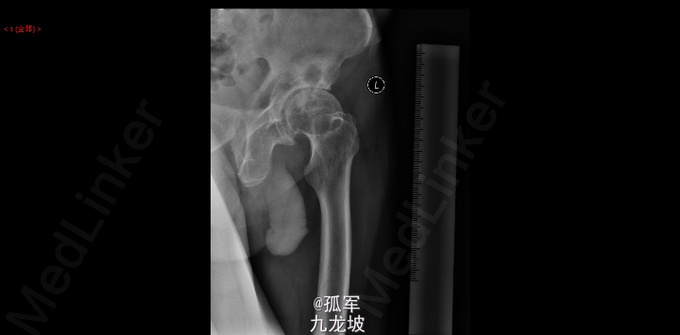

患者跛行步入病房 左侧:腹股沟中点压痛(+),大转子外侧叩击痛(+),左下肢轴向叩击痛(-)。 左髋:4字试验(+),Thomas征(-),滚动试验(+),Trendelenburg征(-)。 髋关节活动范围:左髋130°屈曲<->伸直0°,15°内收<->30°外展,15°伸直内旋<->20°伸直外旋。 骨盆正位片(2015-03):考虑左侧股骨头缺血坏死伴左髋关节退行性变,右侧股骨头缺血性坏死早期改变待排;